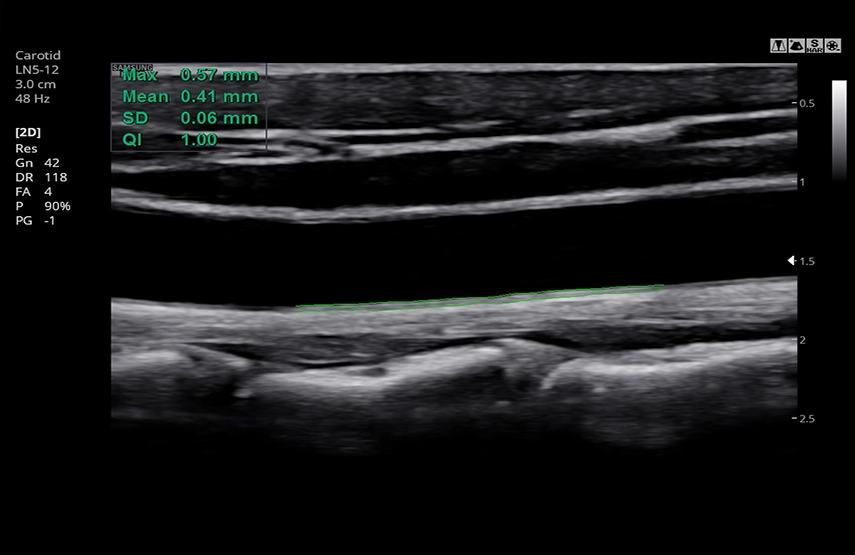

- Auto IMT+ – автоматическое вычисление комплекса интима-медиа общей сонной артерии (Intima Media Thickness). Данная оценка имеет большое значение для ранней диагностики атеросклероза и оценки риска развития инсульта и инфаркта миокарда;

- Линейный датчик LN5-12, 5-12 МГц, апертура 38 мм;

CCA c AutolMT+